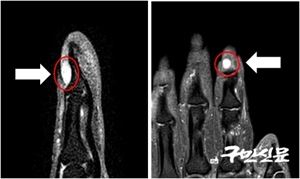

°­µ¿¼º½Éº´¿ø, °Ü¿ïö ¼Õ³¡ ±Ø½ÉÇÑ ÅëÁõÀÌ ´À²¸Áø´Ù¸é »ç±¸Ã¼Á¾¾ç ÀǽÉ

Á÷ÀåÀÎ ¿À¾¾(29¼¼)´Â °Ü¿ïÀÌ µÎ·Æ´Ù. ¾î´À ³¯ºÎÅÍ ¼Õ³¡¿¡ Â÷°¡¿î ¹Ù¶÷À̳ª ¹°ÀÌ ´êÀ¸¸é ¹Ù´Ã·Î ¼ÕÅé ¹ØÀ» Â´Â µíÇÑ ±Ø½ÉÇÑ ÅëÁõÀ» ´À³¢±â ¶§¹®ÀÌ´Ù. º´¿ø...